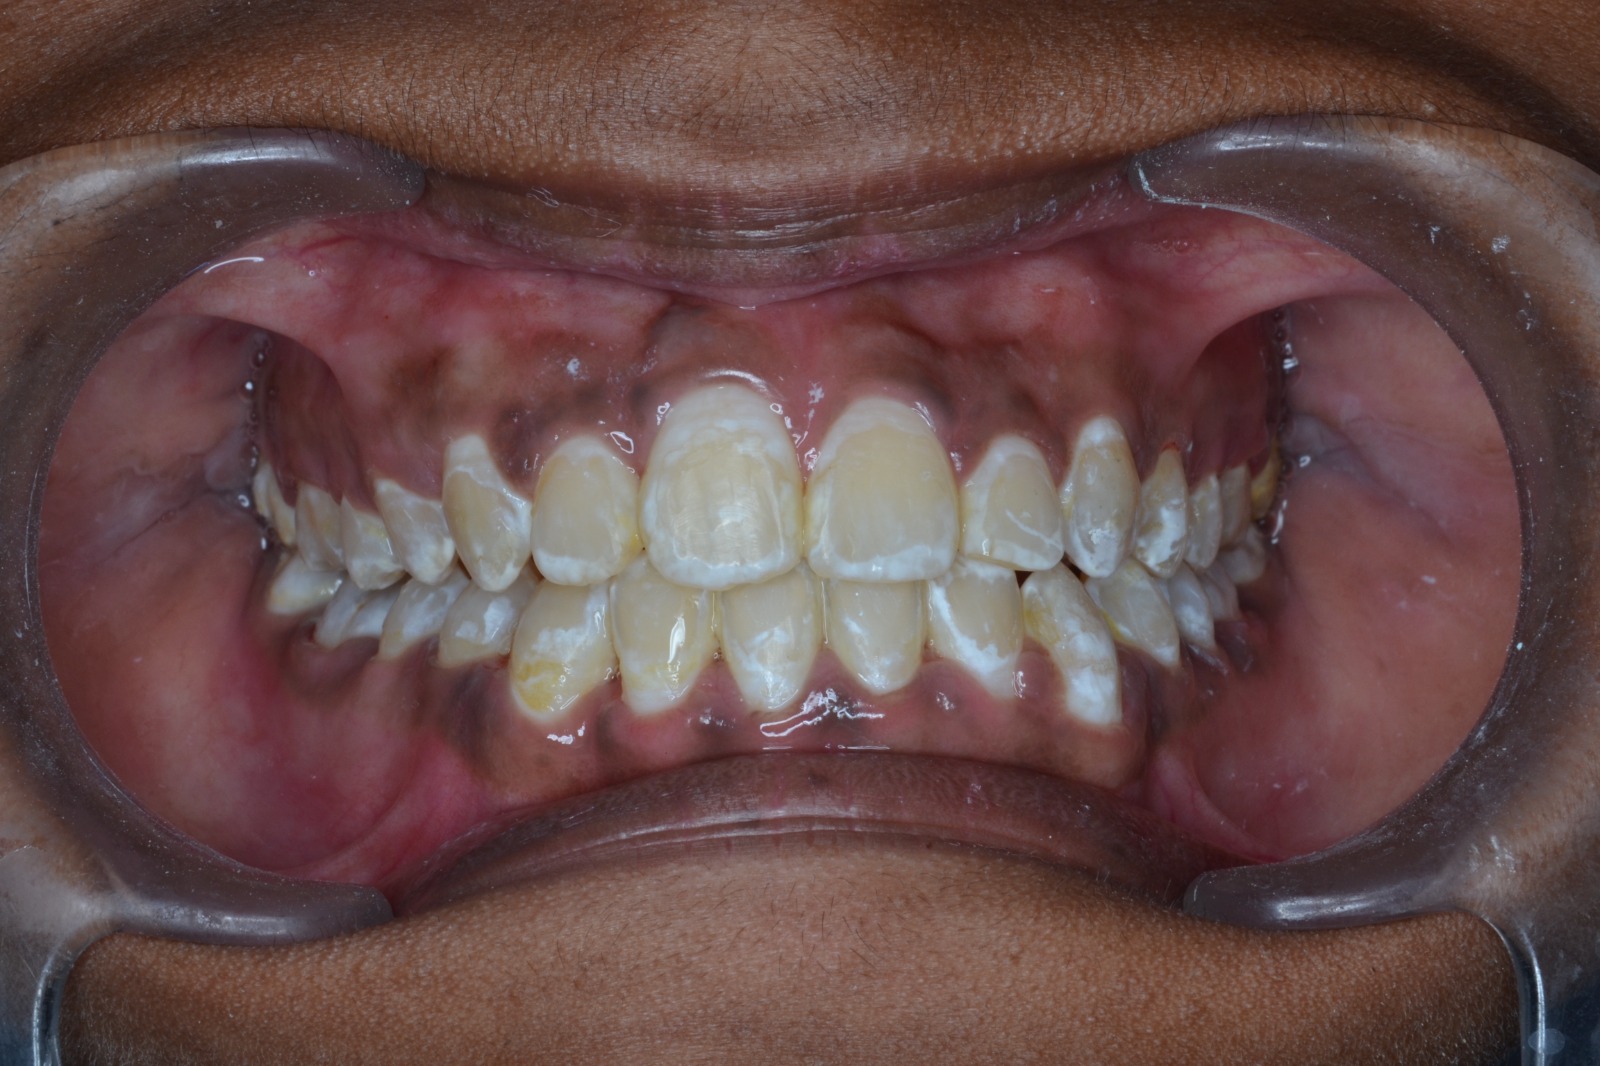

Sairam dental care located in Dharmapuri, with Leading Dentist In Oddapatti, is the Dental Hospital with exclusive root canal, Braces & Invisalign center. Led by renowned Drs Raghuraaman ( Periodontist) and Nivetha Raghuraaman ( Orthodontist) Sairam dental care offers gum treatment with expertise in laser, root canal treatment and digital smile correction with advanced technology aim to focus on aesthetics, comfort and precision. The clinic also specializes in Invisalign treatment, digital smile makeover, laser gum care, dental implants, root canal therapy, extractions and full-mouth rehabilitation blending compassionate care and clinical excellence.

We treat our patients with latest equipment and modern technology, so that they have a very comfortable and pleasant experience.